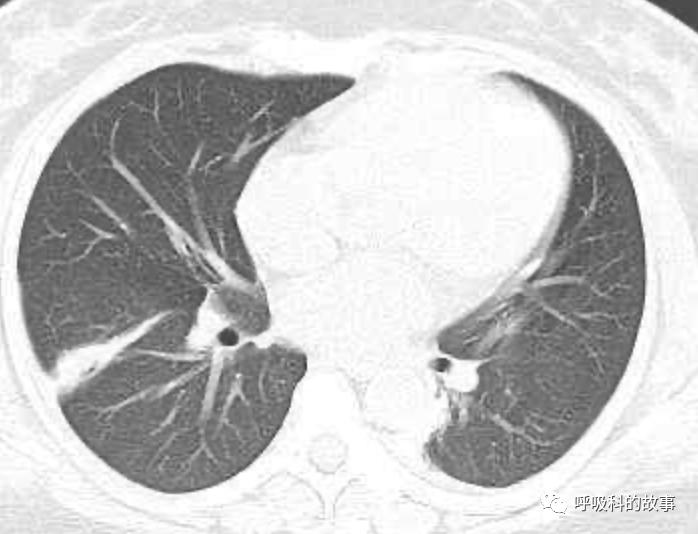

可是在6月26日(往院第18天)仍持续发热的情况下复查肺部CT,肺部病灶已明显吸收了。那么患者发热的原因到底是什么呢?为什么患者高热的情况下血白细胞不升反降,C反应蛋白也没有明显增高?这个时候消化科医生也迷茫了,这可怎么办?于是请感染科和呼吸科医生一起会诊,共商计策。